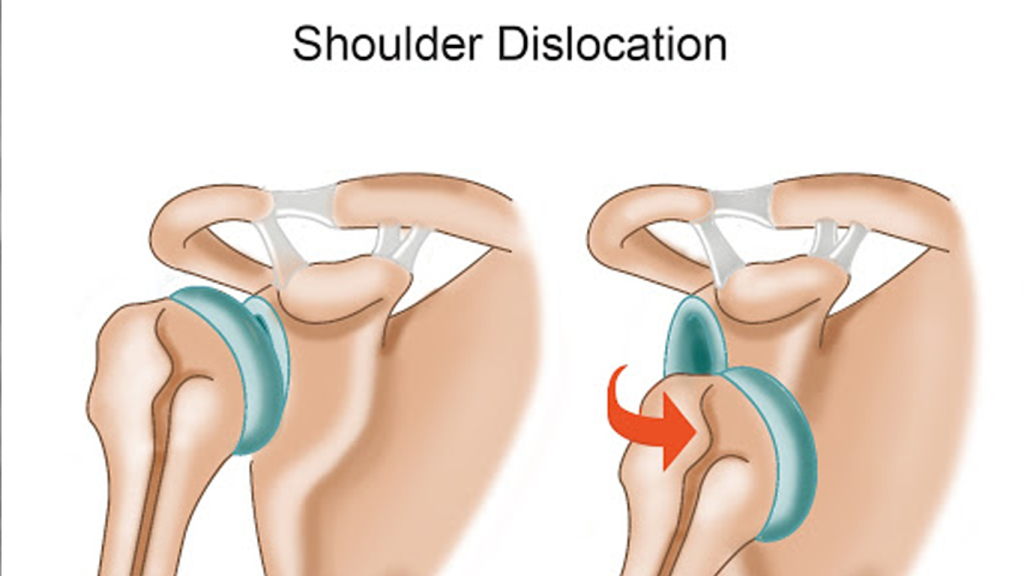

در رفتگی کتف چیست؟

دررفتگی کتف یکی از آسیبهای شایع مفصل شانه است که معمولاً در اثر ضربه شدید یا حرکت ناگهانی بازو رخ میدهد. در این حالت، سر استخوان بازو از جایگاه طبیعی خود در حفره گلنوئید خارج میشود و باعث درد شدید، تورم، و ناتوانی در حرکت دادن شانه میگردد. این آسیب میتواند به اعصاب و رباطهای اطراف نیز صدمه بزند و در صورت عدم درمان مناسب، احتمال دررفتگیهای مکرر را افزایش دهد. درمان شامل جا انداختن مفصل توسط پزشک، بیحرکتسازی شانه، و انجام فیزیوتراپی برای بازیابی عملکرد طبیعی است. پیشگیری از این آسیب با تقویت عضلات شانه و پرهیز از حرکات پرخطر امکانپذیر است.

دررفتگی کتف معمولاً در اثر وارد شدن نیروی شدید یا حرکت ناگهانی به مفصل شانه رخ میدهد که باعث خارج شدن سر استخوان بازو از حفره گلنوئید میشود. این آسیب اغلب در ورزشهای تماسی، سقوط روی دست باز، یا تصادفهای رانندگی دیده میشود. همچنین ضعف عضلات اطراف شانه، شل بودن رباطها، یا سابقه دررفتگی قبلی میتواند خطر بروز مجدد آن را افزایش دهد. مفصل شانه به دلیل دامنه حرکتی بالا، نسبت به سایر مفاصل بدن بیشتر مستعد دررفتگی است و نیازمند مراقبت و تقویت عضلات برای پیشگیری از آسیبهای احتمالی است.